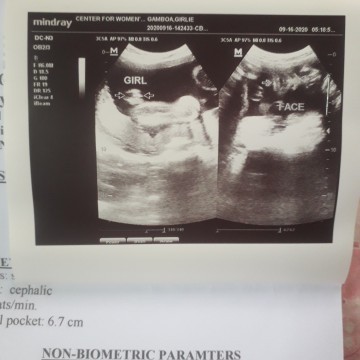

its a baby girl🥰